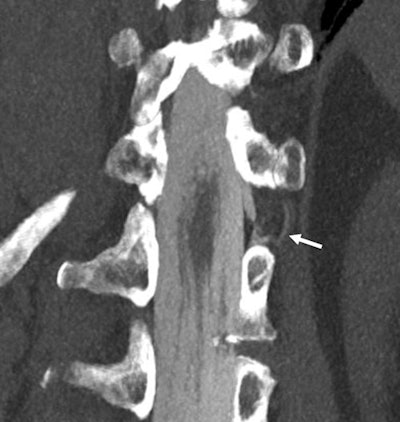

Minnies 2022 winner: Coronal 3-mm maximum intensity projection image of a CSF-venous fistula on a photon-counting CT scanner with 0.2-mm resolution. Image from Dr. Fides Schwartz et al, of Duke University.

The winning image is a coronal 3-mm maximum intensity projection image of a cerebrospinal fluid (CSF) venous fistula (CVF). This fistula was not detected on a regular clinical CT system with a 0.6-mm resolution but was clearly depicted on a Naeotom Alpha photon-counting CT scanner with 0.25-mm resolution, according to a group led by Dr. Fides Schwartz of Duke University in Durham, NC.

CVF can be difficult to visualize, Schwartz and colleagues wrote in a report published April 18 in JAMA Neurology. Typically, CT myelography or MRI are used to diagnose lower than normal fluid pressure in the skull (spontaneous intracranial hypotension) -- and thus CVF -- but these modalities don't necessarily identify the site of the fistula, which can be found anywhere along the axis of the central nervous system and is usually no more than 1 mm to 2 mm wide, the group explained. Photon-counting CT could thus allow for accurate diagnosis of CVF, which is typically treated with epidural blood patches.

In this particular application, the goal of the imaging was to see a very tiny -- perhaps smaller than 1 mm -- connection of the cerebrospinal fluid to the extrathecal space, which in this specific case, is a vein, Schwartz told AuntMinnie.com. These fistulas or leaks are detected by injecting contrast into the spinal canal, usually via lumbar puncture, and then acquiring myelography images on CT.

"Patients often have to be imaged repeatedly in different positions such as lying on their left side and then their right side so the contrast shows where the cerebrospinal fluid is leaving the thecal sac," she noted. "[Photon-counting CT] provides both higher spatial (0.2 mm vs 0.6 mm on most other CTs) and contrast resolution, so these tiny connections can be seen more easily or in this case at all."

Schwartz believes this image was well-received because it shows a very compelling use case for this new technology of photon counting in a disease that is still in the process of being understood.

"Many people might have heard that photon-counting CT is a new imaging technique but not have had the opportunity to actually see images from such a CT scanner," she said. "I think this case can help give people an idea of how the new technology can be applied. The patient population that suffers from spontaneous intracranial hypotension still faces many challenges in getting diagnosed and treated and that is in large part because our current imaging methods are not able to show enough detail."

There are many areas of active research in which photon-counting CT can be applied, she continued. The increased spatial resolution may help detect tumors and metastases at earlier stages or help with more precise staging, which may have immediate impact on treatment and survival for many patients. In addition, photon-counting CT has higher contrast resolution and can be used to lower radiation dose for most patients without losing image quality, which is especially important in children. For patients with larger bodies, it offers the potential to keep radiation dose the same but produces much better image quality, which may ultimately lead to better diagnostic capabilities.

Schwartz's team plans to continue investigating photon-counting CT in as many applications as possible. The group is currently working on quantifying the benefit of using the technology in myelograms of patients with spontaneous intracranial hypotension through automated image analysis and reader studies.

"We are excited to explore other applications in neuroradiology and our abdominal section is very actively involved in research using photon-counting CT, too," she said.